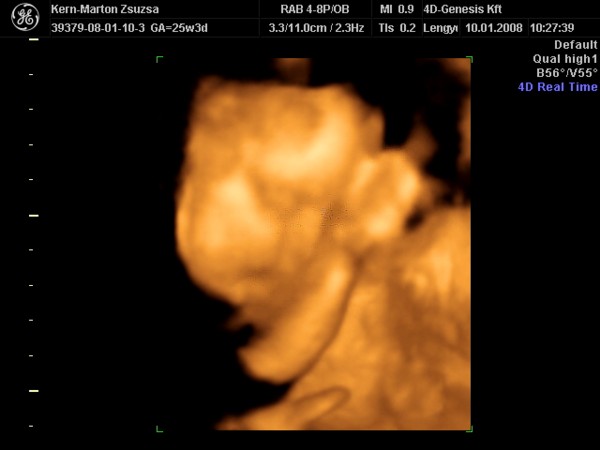

Zsu,tényleg nagyon jól sikerült elkapni az első képen a lánykádat.Azt tudom,hogy kis vöröske Kata,de a 2 kép közül melyik az "igazi" vagy legalábbis melyik hasonlit jobban rá?Tudom,hogy a fényképező rengeteget csal